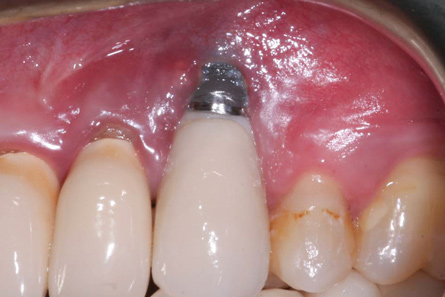

The results of these studies suggest that the shorter the prosthetic abutment height, the greater the amount of MBL that can be expected with bone-level implants (Figure 2). While these studies only measured MBL, it may be surmised that similar MBL patterns would develop on the facial and lingual aspects when the prosthetic abutment height is less than 2 mm. With greater MBL, the risk for bacterial colonization of the implant surface may increase. It would seem prudent, therefore, to place the crown margin in a position that would minimize MBL.

Fig 2. The height of this abutment was less than 2 mm on the facial. This may have led to additional marginal bone loss. Bacterial colonization of the abutment and the exposed implant body resulted in peri-implantitis.

Figure 2